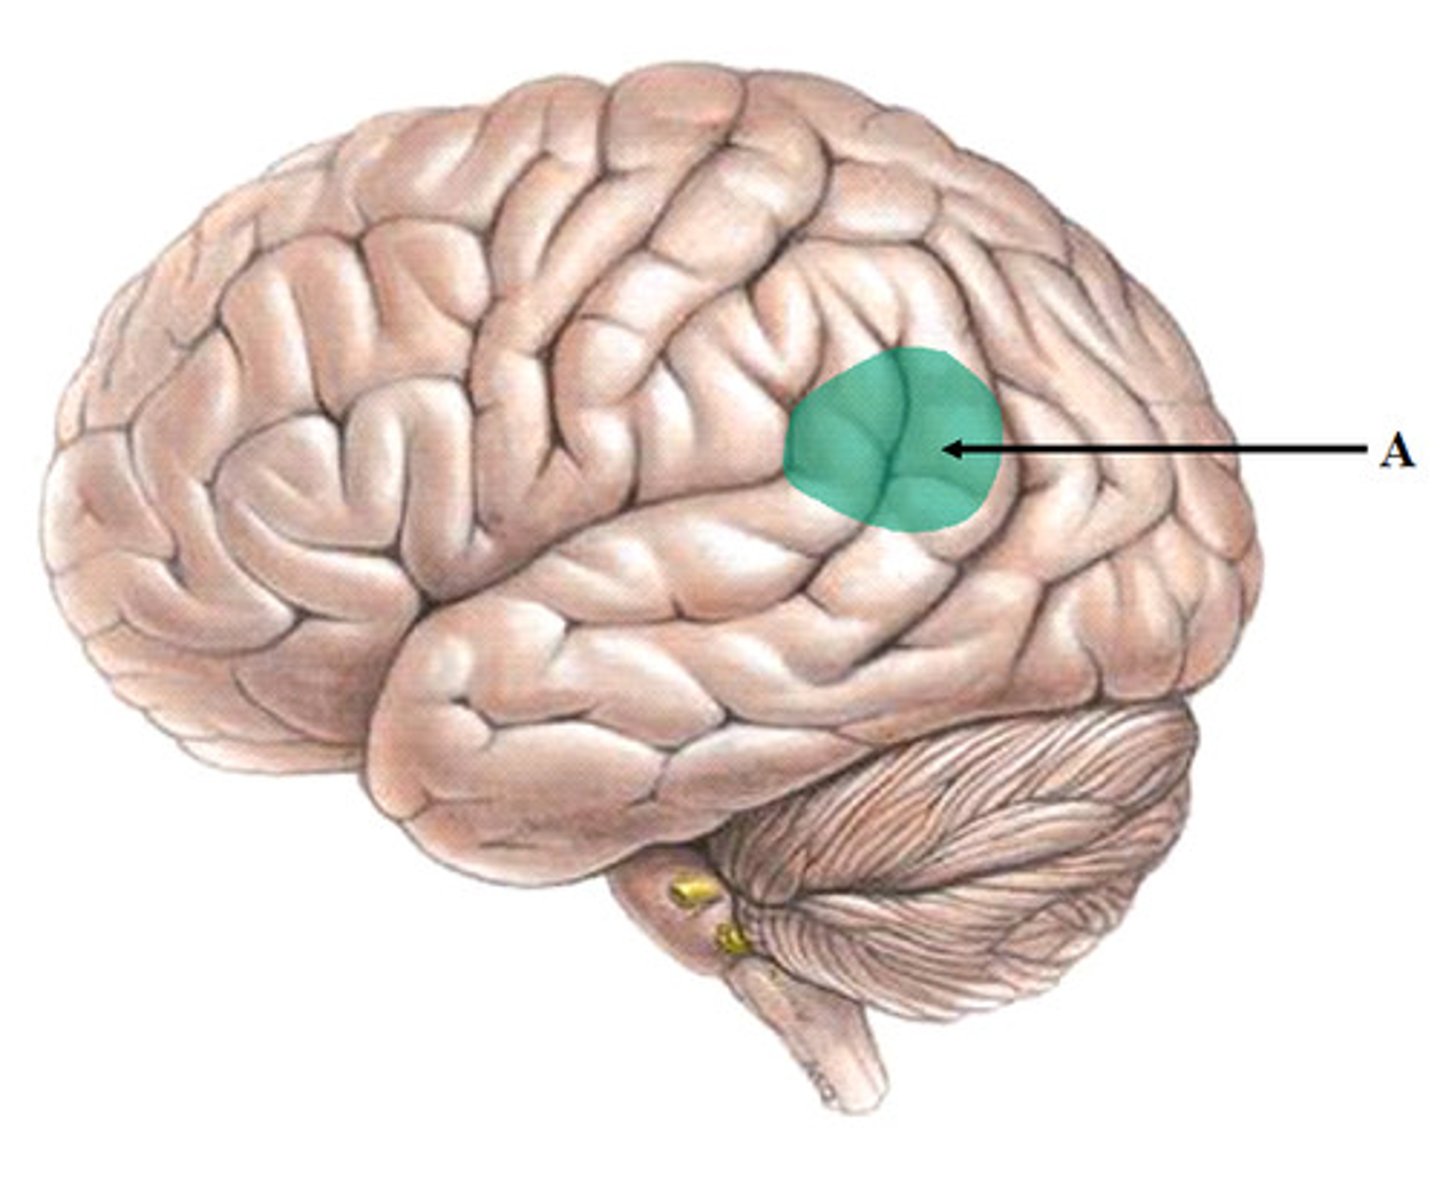

broca's area

speech production